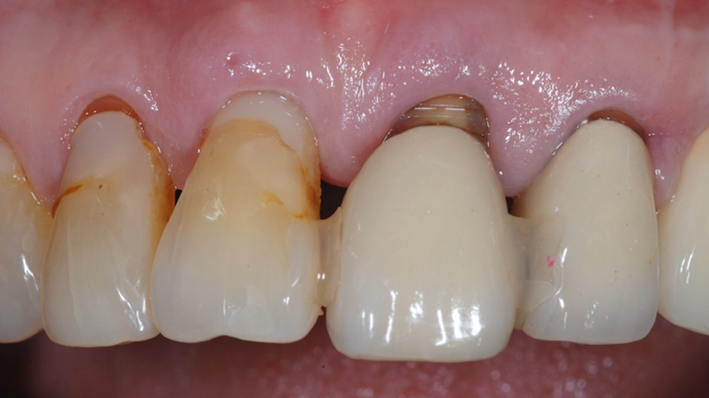

Clinical case: : R2GATE guided surgery & immediate implant placement

- Courtesy of Dr. Kwang Bum Park, Korea -